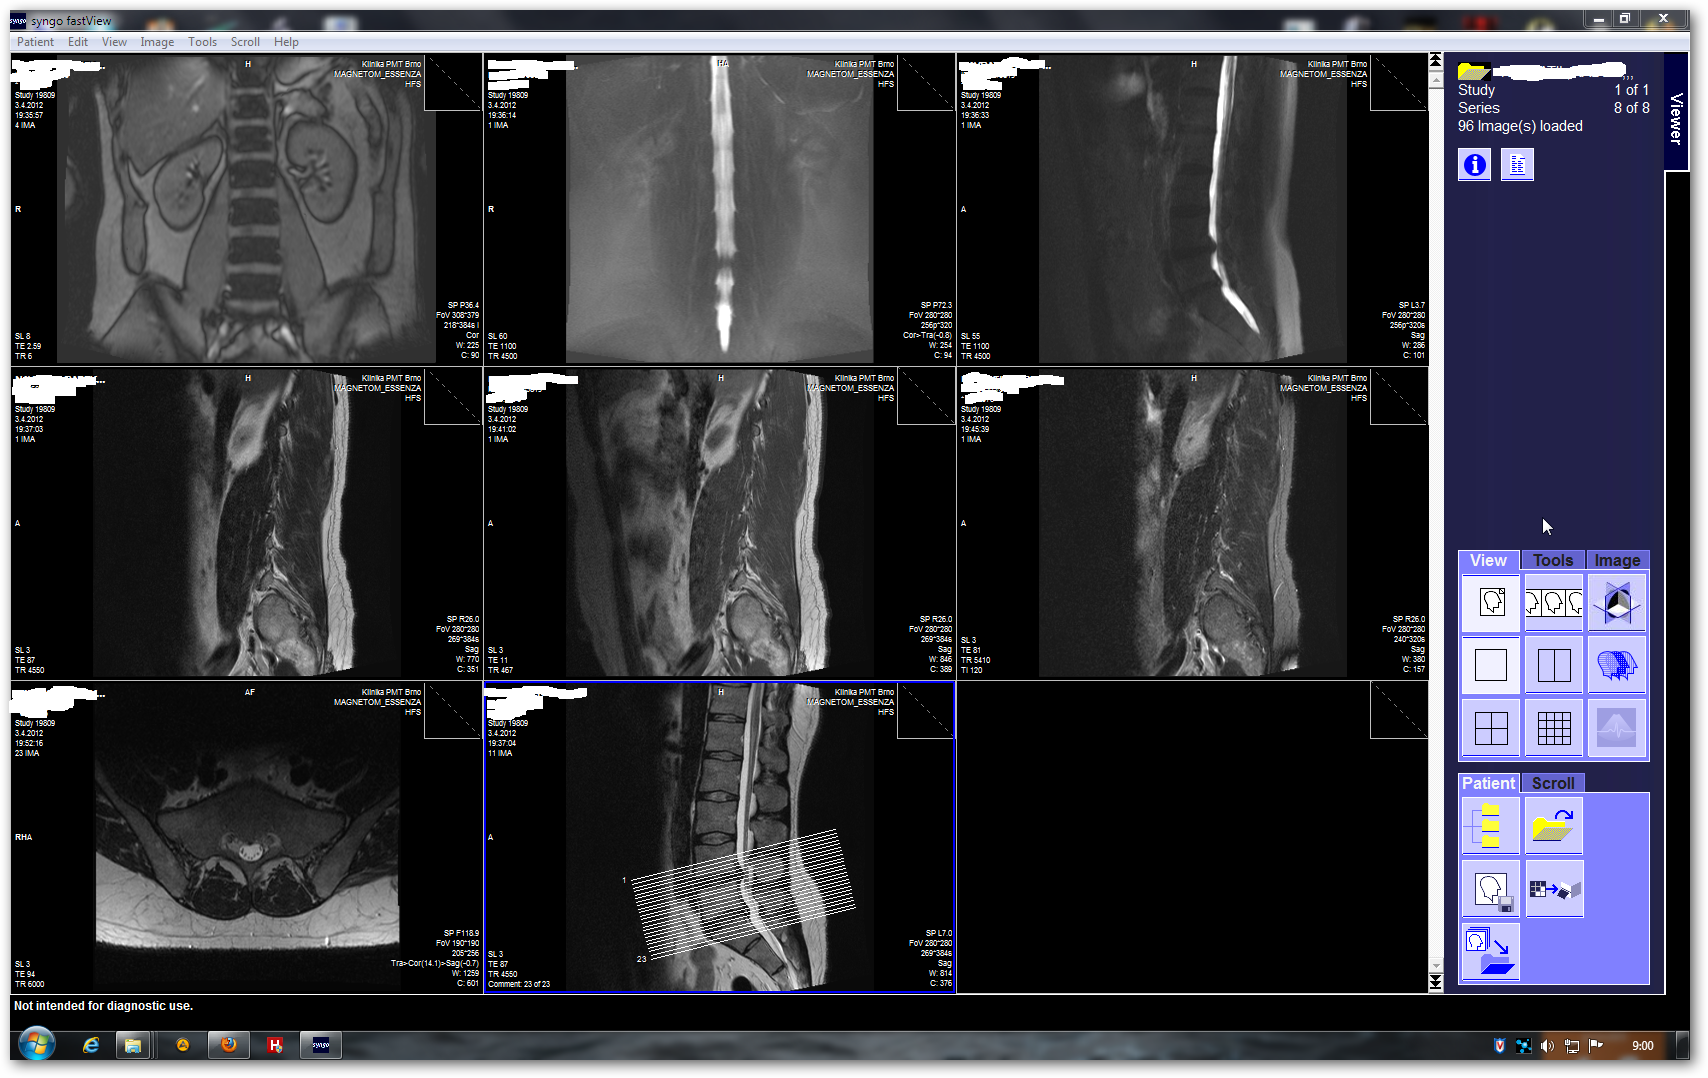

Nemužu dostat obsah z DVD do komplu,abych ho následně vypálil.Je to Magnetická rezonance v prohlížecím programu Syngo.Takhle vypadá,když se načte z DVD(obr8).Tohle mám po pokusech o zkopčení,jen prázdná okénka(obr7)

Zkoušel jsem přetáhnout složky,vytvořit obraz disku,použít Shrink.Obrázky se zobrazí pouze pokud mám DVD v mechanice.Domnívám se,že to nefachčí,protože bych potřeboval ten samotnej sofware.Ten jsem nikde ke stažení nenašel(pochopitelně).Každej ten snímek z obr8 jde zvetšit a pomocí kolečka mysi se posunuje po krocích,takže má v sobě dalších cca 10 fotek.(obr 9a10)